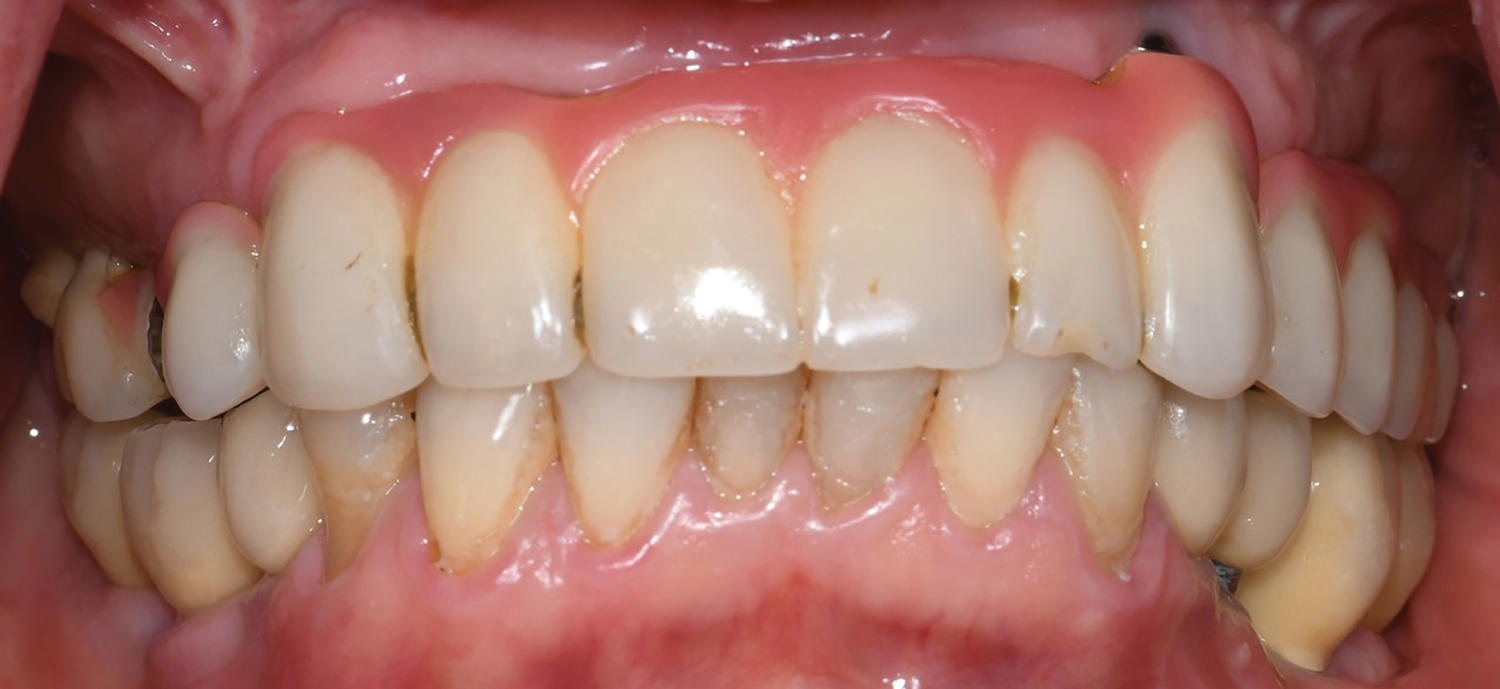

Fig 20. Frontal view at 20-year follow-up.

Figure 20

In 2020, the patient presented to the NYUCD Periodontology and Implant Dentistry Clinic. A clinical examination and radiographic evaluation showed that the patient's maxillary arch still exhibited good peri-implant soft-tissue health and stable marginal bone level with slight bone loss on implants Nos. 2, 6, 8, and 11 (Figure 18 through Figure 20). The maxillary prosthesis showed adequate stability with a slight chipped suprastructure on the porcelain on the right side. The patient was advised to substitute the implant-supported, screw-retained hybrid acrylic complete denture in the maxilla with a fixed, implant-supported, screw-retained prosthesis, which she declined due to financial considerations.